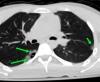

На представленных СК-томограммах на электронном носителе органов грудной полости пациента А №4473 от 23.09.20254 года, №4478 от 24.09.20254 года, №4511 от 28.09.20254 года - визуализируется перелом средней трети левой ключицы по типу «зеленой веточки», без смещения отломков, без признаков консолидации. В грудине дифференцируются зоны роста. Данных за перелом грудины, ребер, грудных позвонков не выявлено. Легкие по всем полям с обеих сторон прилежат к грудной клетке. Данных за пневмоторакс не выявлено. Бронхо-сосудистый рисунок несколько усилен. В задне-медианных отделах S6 правого легкого, на уровне тел позвонков Th5-Th8, на фоне обширной зоны контузии легкого примерным размером до 58х52х20 мм визуализируются две воздушные полости неправильной овальной формы, размером до 26х14х6 мм и до 12х10х3 мм. Полости с небольшими уровнями гетерогенного жидкостного содержимого (кровь). В правом легком: в прикорневой зоне, в S8, S9 визуализируется до 5 очагов контузии легкого по типу «матового стекла» размером от 12х10 мм до 20х15 мм. В левом легком: в S1\S2, в S4 визуализируются до 3 очагов контузии легкого по типу «матового стекла» размером от 11х10 мм до 14х9 мм. Диафрагма обычно расположена. В полости перикарда и в плевральных полостях свободной жидкости не выявлено. Заключение: КТ-картина участков разрыва правого легкого в задне-медианных отделах S6; разнокалиберных зон ушиба в обоих легких. Перелом с\3 левой ключицы без смещения. Травматические изменения могут соответствовать сроку травмы в ДТП от 23.09.2025 года

Картинки от рентгенолога